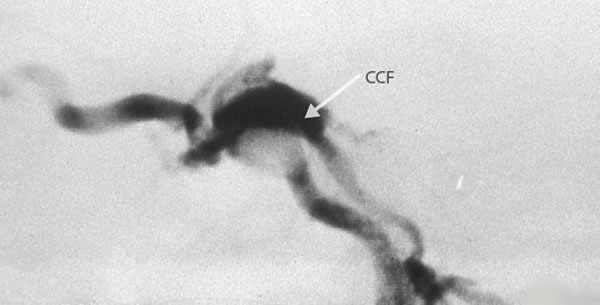

Karotidno-kavernozna fistula je arteriovenski spoj između arterije carotis interne i sinusa kavernozusa.

- angiografija